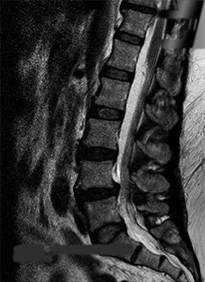

On a sagittal MRI of the lumbar spine, a vertebral body endplate adjacent to a degenerated disc shows hypointense signal on T1-weighted images and hyperintense signal on T2-weighted images. This finding corresponds to which Modic type, and what does it pathologically represent?